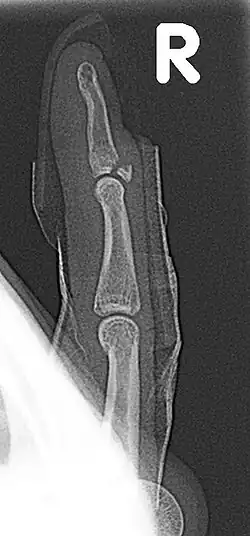

Fracture of the dorsal base of the distal falange by extensor tendon avulsion (Busch fracture) | |

In medicine a Busch fracture[1] is a type of fracture of the base of the distal phalanx of the fingers, produced by the removal of the bone insertion (avulsion) of the extensor tendon. Without the appropriate treatment, the finger becomes a hammer finger. It would correspond to the group B of the Albertoni classification.[2] It is very common in motorcycle riders and soccer joggers, caused by hyperflexion when the tendon is exercising its maximum tension (the closed hand tightening the clutch lever or the brake lever).[3][4]

A Busch fracture, showing the characteristic mallet finger

Busch fracture mechanism: because the bit of bone attached to the tendon has broken off, the tendon can't extend the finger tip